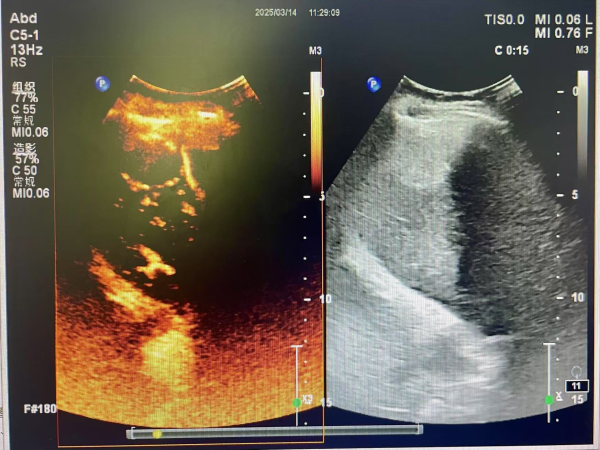

近日,一位65岁患者因在体检时查出肝脏占位病变而就诊于超声功能科,为进一步明确占位病变的良恶性,黄继红主任针对患者情况,充分评估确定患者检查适应症与禁忌症,由黄继红主任医师,游明娟护师为其实施了肝脏声学造影检查,检查医生与执行护师配合默契,整个检查过程顺利进行,患者无任何不适,为确保安全,患者留观30分钟,亦无任何不适后安返,超声造影提示:良性病变,肝血管瘤。患者悬着的心也得以平静,为其后续诊疗提供可靠依据。

脏器声学造影,是近年超声领域快速发展的新技术,被誉为超声医学发展的“第三次革命”。是一种利用超声造影剂与超声成像技术相结合的检查方法。通过外周静脉注射超声造影剂,使病变内部小血管和低速血流更清楚显示,显著提高超声诊断的分辨力、敏感性和特异性,这种技术不仅具有无创、无痛、无辐射,操作方便的优点,而且实时性强,能够提供丰富的诊断信息,使得大量常规检查无法明确诊断的病例得以确诊。